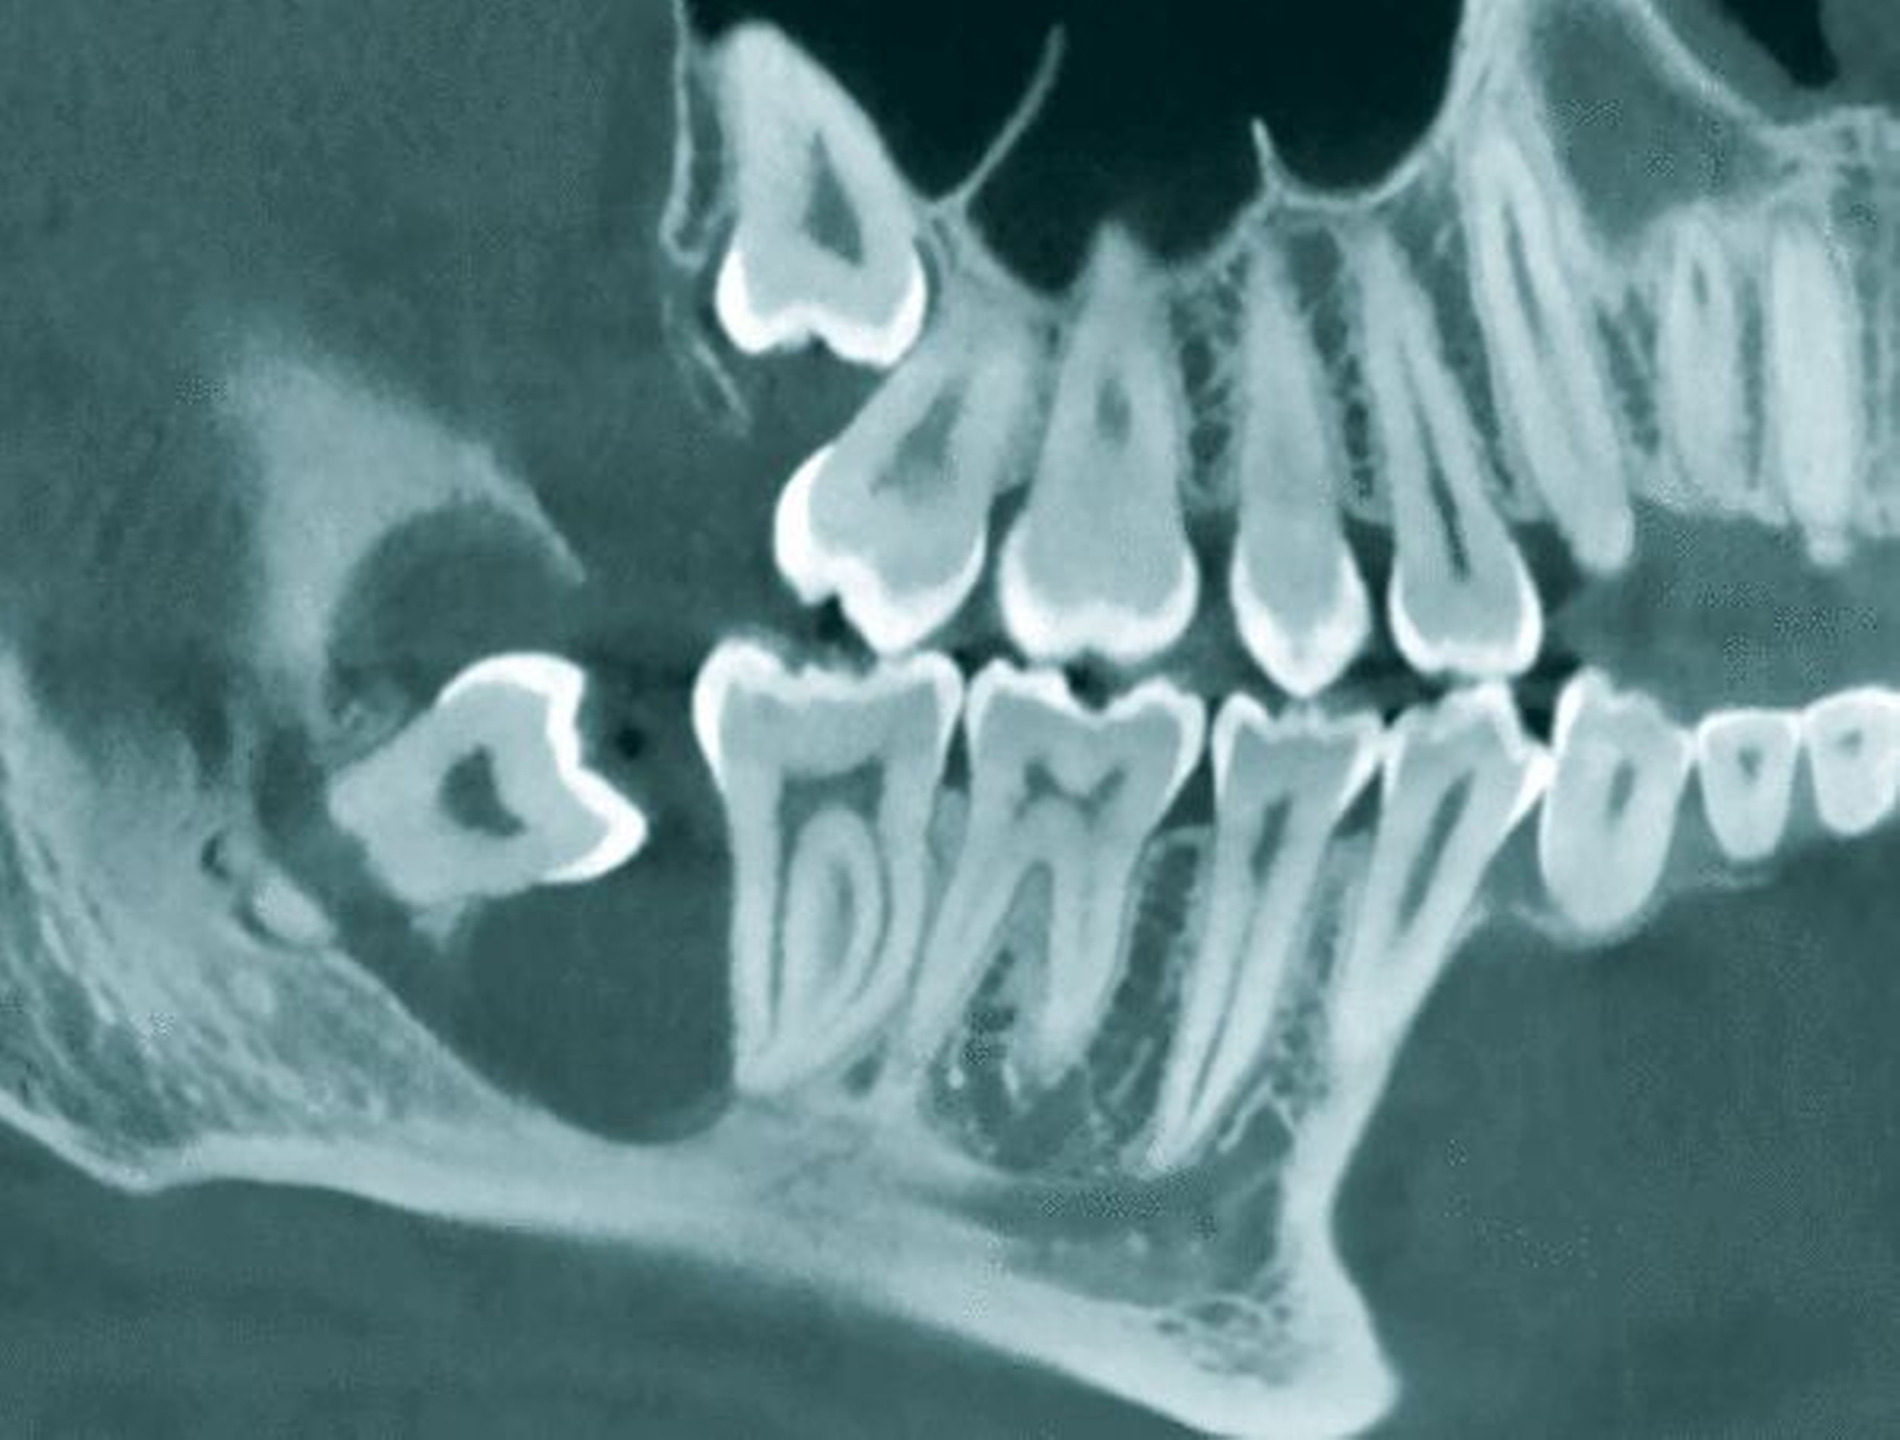

Hintergrund:Mit der digitalen Volumentomografie (DVT) ist die dreidimensionale Bildgebungs-methodik für die Indikationsstellung und Behandlung innerhalb der Zahnheilkunde, Oralchirurgie und Mund-, Kiefer- und Gesichtschirurgie mittlerweile etabliert worden. Die Vorzüge der DVT-Diagnostik im Hinblick auf topografische Information, Auflösung und Dimensionsgenauigkeit sind in den letzten Jahren umfangreich beschrieben worden. Mit der Verfügbarkeit des DVT hat die Frage nach der Notwendigkeit einer 3-D-Diagnostik vor der operativen Weisheitszahnextraktion eine zentrale Bedeutung.

In mehreren Studien wurde gezeigt, dass das DVT geeignet ist, morphologische Besonderheiten, Lageanomalien und insbesondere auch die fehlende Abgrenzung zwischen Zahnfach und Nervkanal darzustellen und damit für die Einschätzung des Risikos einer Nervschädigung geeignet ist [Ghaeminia et al., 2009; Lübbers et al., 2011; Neugebauer et al., 2008; Suomalainen et al., 2010; Sursala and Dodson, 2007; Tantanapornkul et al., 2007].

Aus der Tatsache, dass diese Merkmale in der 3-D-Bildgebung gut dargestellt werden können, leiten die Autoren dann jeweils die Indikation einer präoperativen 3-D-Bildgebung ab. Daneben gibt es erste Hinweise, dass die chirurgische Vorgehensweise durch die Einbeziehung der DVT-Informationen im Einzelfall verändert werden kann [Ghaeminia et al., 2011]. Außerdem lassen sich kritische Befunde wie die Resorption von 12-Jahr-Molaren durch retinierte Weisheitszähne nur in dreidimensionalen Bildgebungsverfahren bewerten [Oenning et al., 2015].